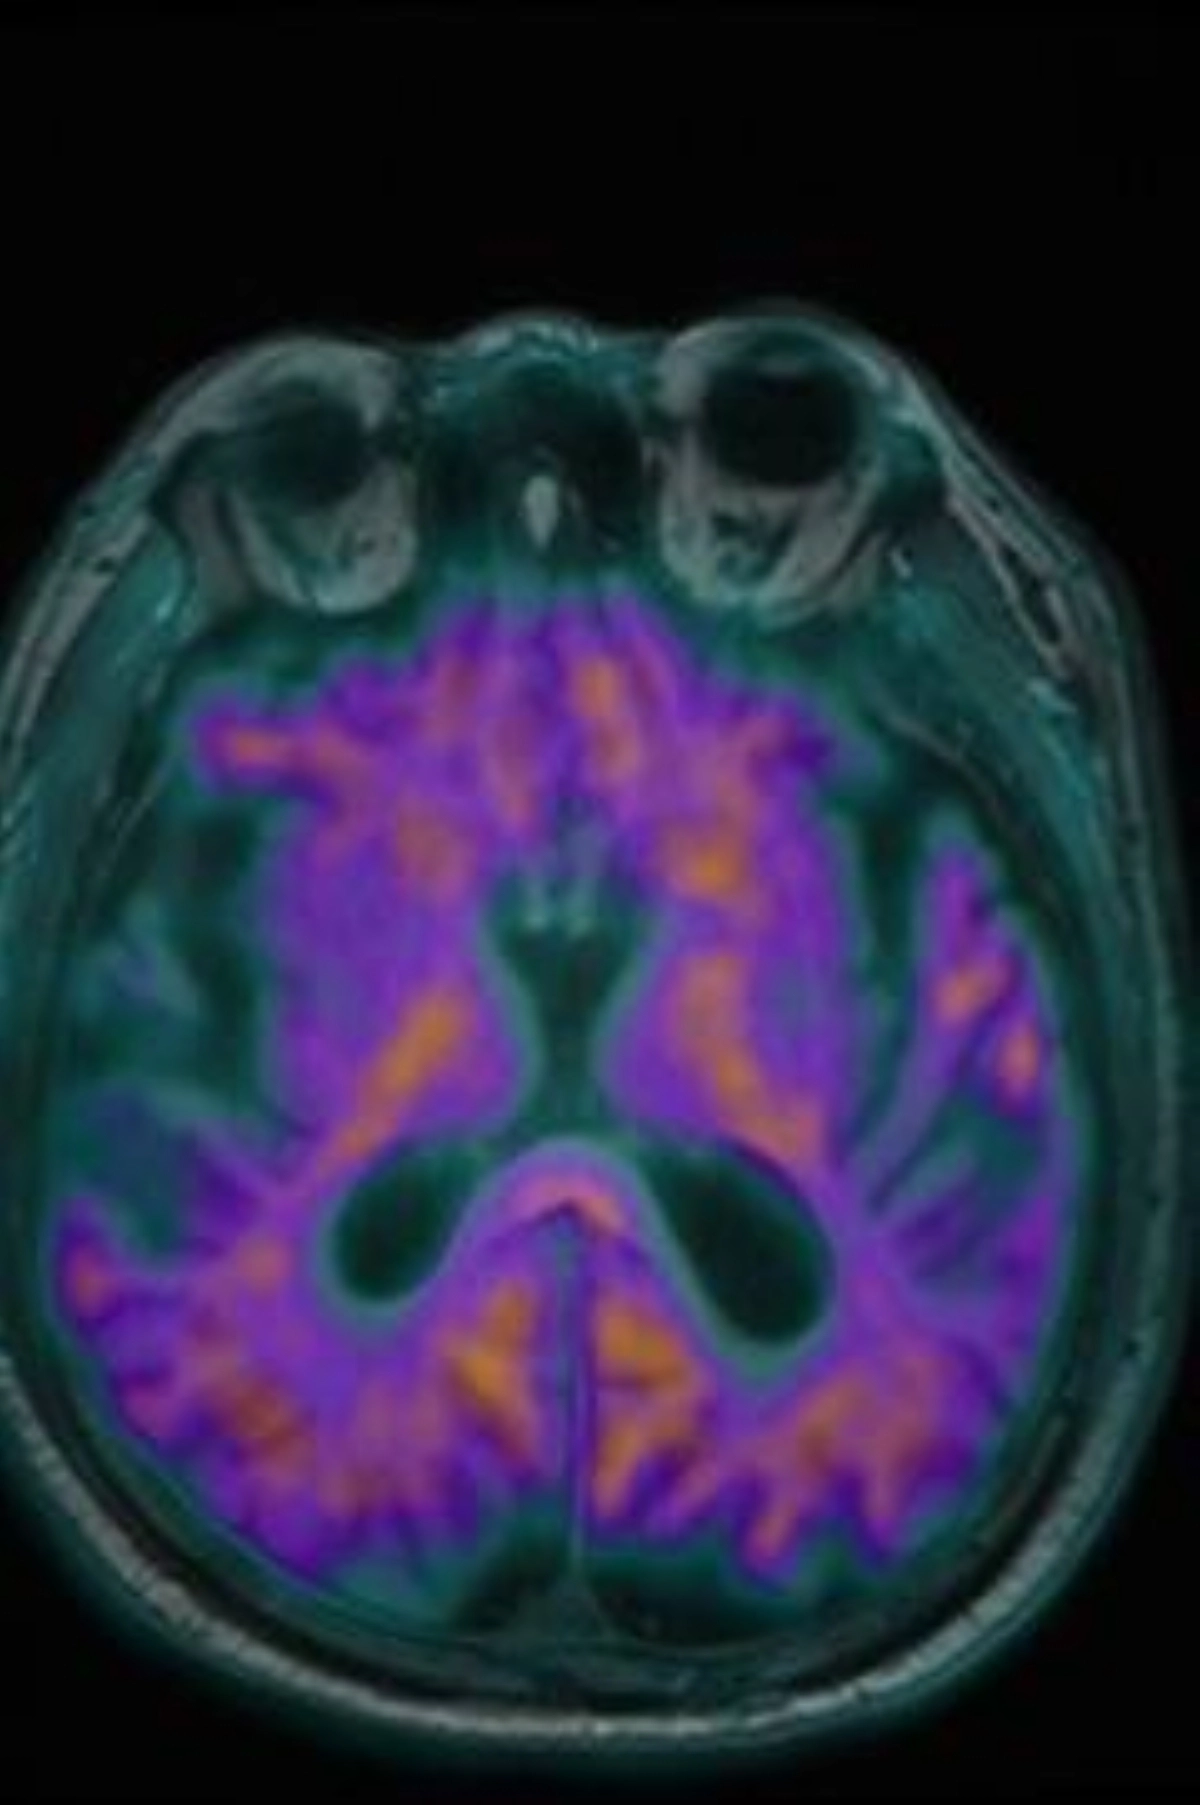

دشن مركز التصوير الجزيئي I-One، يوم الاثنين 15 ديسمبر 2024م، خدمة التصوير الجزيئي Amyloid PET MRI لتشخيص مرض الزهايمر، وذلك بالتعاون مع شركة Oryx Isotopes لإنتاج مادة Amyloid (18F – FBB).

ليصبح بذلك مركز التصوير الجزيئي I-One، الأول والوحيد على مستوى الشرق الأوسط الذي يقوم بتشخيص مرض الزهايمر باستخدام جهاز المسح البوزيتروني الطبقي المدمج بالرنين المغناطيسي PET/MRI.